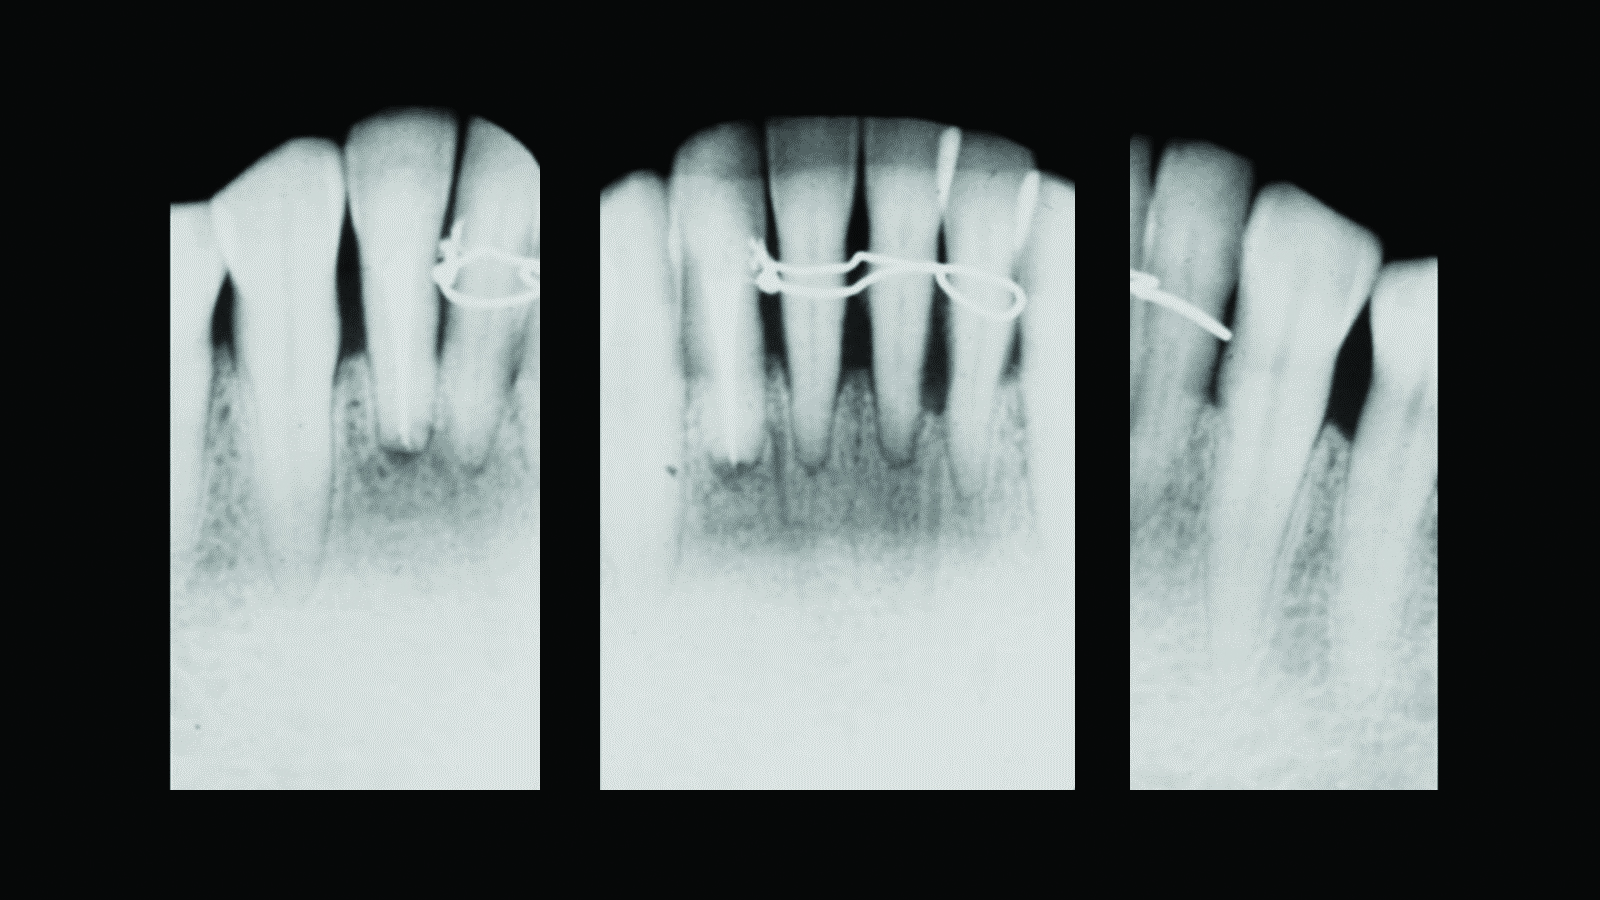

Fig 7. Case 2. Initial presentation of a patient with periodontitis (teeth Nos. 22 through 27). Generalized pocket depths of 6 mm to 7 mm were present, with wire splint on teeth Nos. 23 through 25.

Figure 7

Fig 8. Initial radiograph of the Case 2 patient, teeth Nos. 22 through 27. Fig 9. SRP resulted in the elimination of inflammation and remaining probing depths of 2 mm to 3 mm in Case 2 patient, 3 months post-therapy. (Fig 4 through Fig 9 are courtesy of Dennis Tarnow, DDS.)

Fig 9. SRP resulted in the elimination of inflammation and remaining probing

depths of 2 mm to 3 mm in Case 2 patient, 3 months post-therapy.

(Fig 4 through Fig 9 are courtesy of Dennis Tarnow, DDS.)